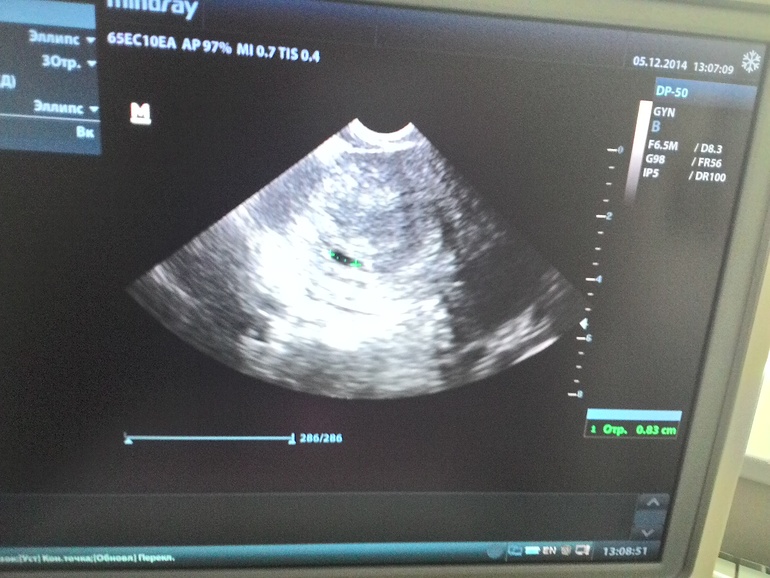

Потом еще пошла 5 декабря - на УЗИ - маленькая бусинка, ХГЧ 10299, срок - 5 недель!!!!!!!!!!!!! УРАААААААААААА!!!!!!!!!!!!!![]()